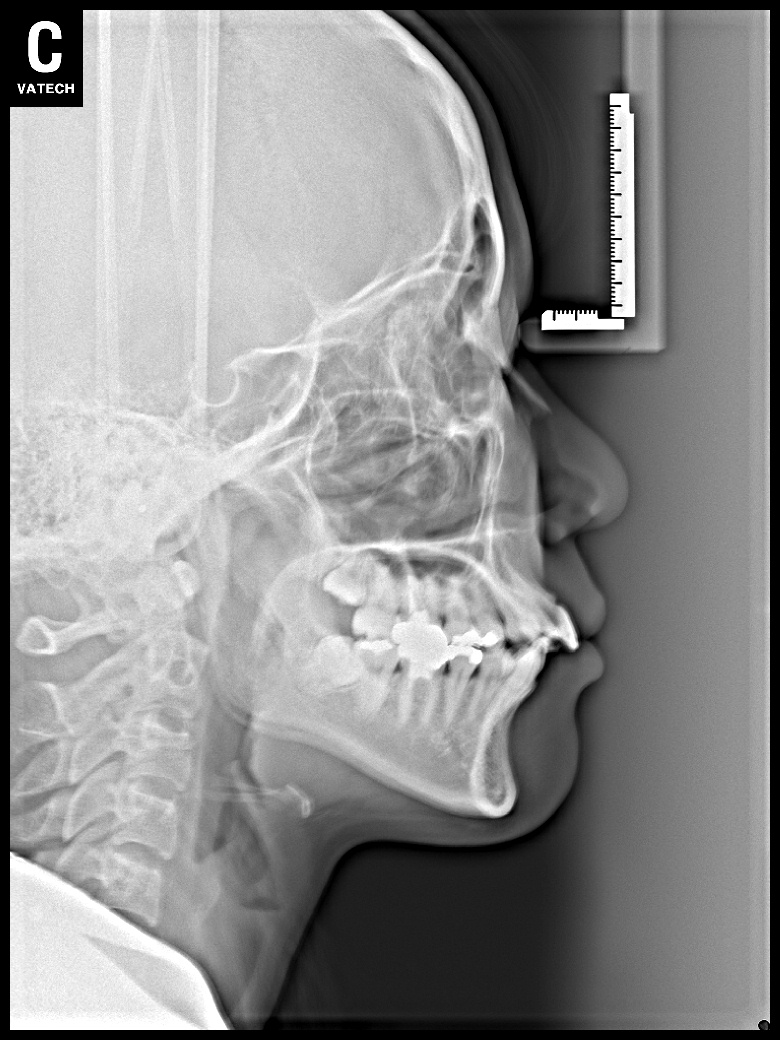

치료 전 사진입니다.